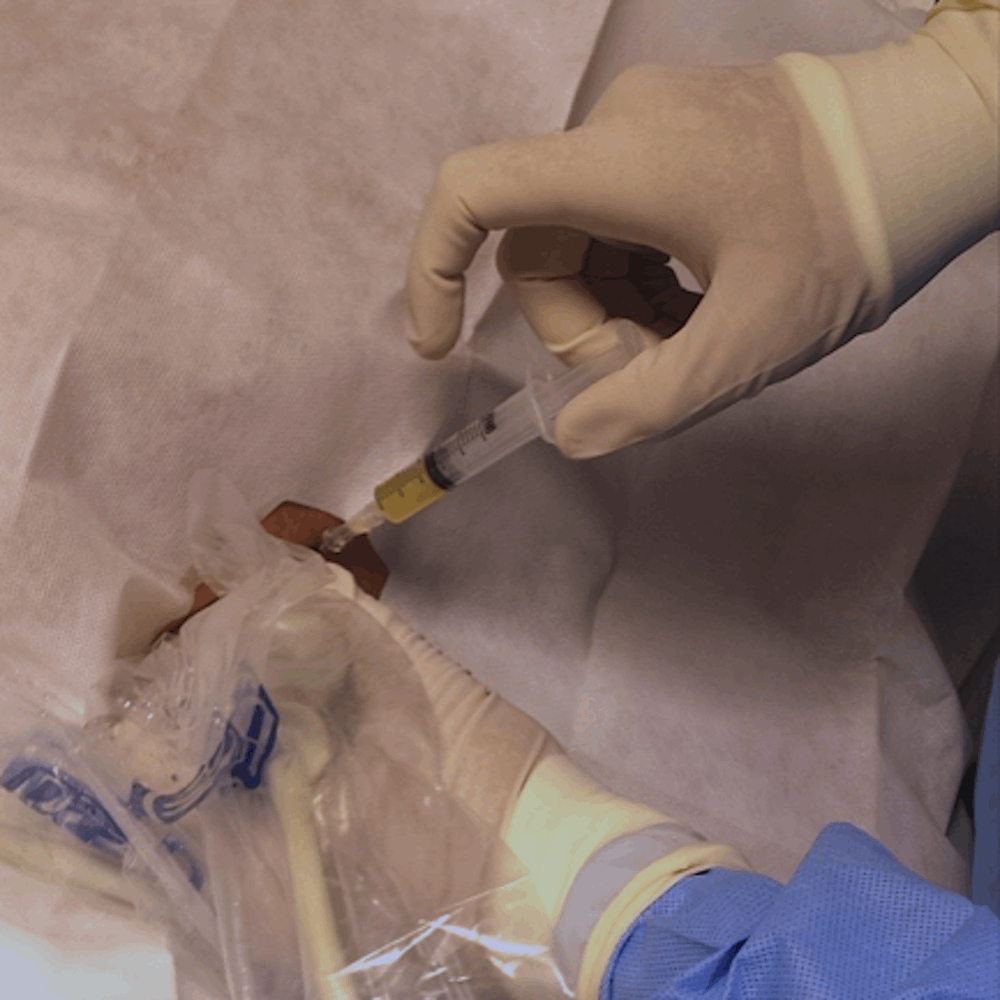

No Instituto Dahmer Rocha, utilizamos tecnologias de ponta e métodos modernos para garantir diagnósticos precisos e confiáveis. Equipamentos de alta performance, aliados a técnicas inovadoras de radiologia intervencionista, permitem identificar condições com rapidez e orientar o melhor tratamento, sempre com foco na excelência e no cuidado personalizado.

O Dr. Rafael é muito atencioso, desde a primeira consulta foi transparente em suas explicações sobre os procedimentos, o que foi muito importante para minha decisão de realizar a embolização do meu mioma uterino com segurança. Ótimo profissional durante todo o processo até a minha recuperação dando atenção para que eu tenha a melhor recuperação possível. Com certeza indico para todos aqueles que procuram essa opção de tratamento! Parabéns 👏 e muito obrigada por tudo!

Fui super bem atendido pela Clínica, desde o início do processo me ajudaram a obter autorização do plano de saúde e me guiaram pelo processo. Dr. Rafael é um profissional qualificado e atencioso, me atendeu super bem, desde a preparação para a cirurgia e depois mostrando-se interessado em acompanhar os procedimentos pós-operatórios. Minha avaliação da clínica, do médico, dos serviços é a melhor possível, inclusive já indiquei para outras pessoas.

Dr. Rafael é um excelente profissional. Seu atendimento detalhado e humanizado me tranquilizou bastante. Procuramos o seu consultório para verificar a possibilidade da realização de ablação tumoral no pulmão já que pela localização não seria indicada a cirurgia convencional, devido a sua complexidade. O procedimento foi realizado no último dia 30 e não tive nenhum tipo de reação adversa. Não senti dores e nenhum tipo de incômodo. Fiquei internada por apenas uma noite, porque já era um pouco tarde para dar alta. Meus amigos e familiares ficaram surpresos ao me ver tão bem e confesso que eu também. Espero de coração que mais pessoas sejam agraciadas pelas mãos do Dr. Rafael.

O dr. Rafael me foi indicado como um médico diferenciado, o melhor para o caso do meu pai, um senhorzinho de 86 anos com câncer no fígado, para fazer o procedimento de químio embolização. Realmente: ele tem muito conhecimento e experiência, o que nos deixou muito seguros e tranquilos quantos ao sucesso do procedimento. Mas o que mais nos impressionou foi o tratamento humano desde o primeiro contato, a preocupação com o meu pai desde antes de decidirmos pelo procedimento e pelo acompanhamento após a químio. Entrou em contato praticamente todos os dias para saber como meu pai estava reagindo a medicação, tanto pessoalmente como através da secretária Laine, extremamente atenciosa e competente em todos os contatos. Parabéns a equipe e muito obrigada por tudo! Agradeço muito a Deus por Ele ter colocado anjos como a equipe do dr. Rafael nas nossas vidas.

Desde o primeiro contato já pude perceber a excelente cortesia no atendimento. Percebe-se não sermos apenas mais um paciente e sim um ser humano que está precisando de auxilio médico. Nas conversas com Laine e Dr Rafael se pode sentir vocação profissional o que nos dá total confiança e segurança. Não mediram esforços para proporcionar todos os meios que facilitassem o andamento do processo de Embolização Prostática já que não resido em Joinville. Dr. Rafael, tanto previamente quanto pós procedimento, além de praticamente nos dar uma aula sobre o mesmo, mantém um contato frequente, mesmo distante geograficamente, aumentando assim nossa confiança e acelerando o processo de recuperação. Saliento a indicação de Mabli que assessorou junto ao plano de saúde. Sempre terei gratidão a toda equipe do Dr. Rafael assim como também àquelas pessoas que auxiliaram no Hospital da Unimed Joinville.

Tenho uma profunda gratidão pelo profissionalismo e humanidade no procedimento de ablação do rim esquerdo realizado pelo Dr. Rafael. Desde a consulta, senti a empatia e preocupação com o meu bem-estar. Dr. Rafael explicou com clareza o procedimento e os possíveis riscos e me tranquilizou com suas palavras. Durante a cirurgia foi extravagante cuidadoso e atencioso e acompanhou de perto minha recuperação. Na alta, que foi no mesmo dia, falou com minha esposa explicando o procedimento. Tem a minha gratidão por sua dedicação e competência. Que Deus abençoe a ele e sua família.

Doutor Rafael é meu médico desde 2022. Recentemente fiz uma radioablação de tumores no fígado com ele, e anteriormente uma quimioembolizacão de outro tumor maior. Ele é simplesmente sensacional, eficiente, empático, me sinto segura nas consultas e nos procedimentos. Ele não mede esforços pra trazer o que tem de melhor na medicina pra ajudar a me tratar. Nunca deixou de poupar esforços pra me deixar confortável no pré e pós operações, é um médico disponível e cuidadoso com o paciente e a família também. A secretaria do doutor também tem que ser elogiada, pela prontidão e suporte. Eu não poderia pedir a Deus médico melhor pra me ajudar a passar pelo meu tratamento, sou extremamente grata.